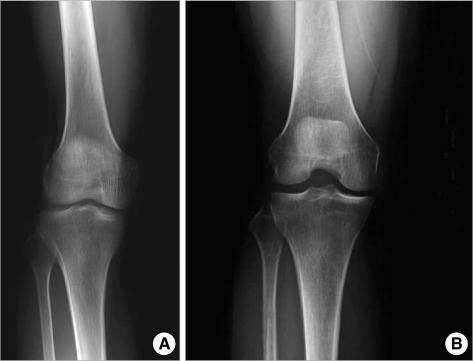

The purpose of this study was to estimate the prevalence of radiographic and symptomatic knee osteoarthritis (OA) among community residents and to elucidate the relevant risk factors. This prospective, population-based study was conducted on residents over 50 yr of age in Chuncheon. Subjects completed an interview based on a standardized questionnaire and clinical evaluation including standardized weight bearing semiflexed knee A-P radiographs. We defined a subject with the Kellgren and Lawrence grade >or=2 as having radiographic knee OA (ROA). Symptomatic knee OA (SOA) was defined by the presence of both ROA and knee pain. We obtained symptom information and radiographs from 504 subjects. The prevalence of ROA and SOA was 37.3% and 24.2%, respectively. The prevalence of both ROA and SOA was significantly higher among women than among men. Multivariate analysis revealed that the presence of hypertension, and a manual occupation were significantly associated with the presence of ROA and SOA. Lower level of education was significantly associated with the presence of ROA, and female sex with the presence of SOA. In conclusion, both ROA and SOA are common in the aged adult population of Korea, with preponderance for women.

本研究旨在评估社区居民影像学和症状性膝骨关节炎(OA)的患病率,并阐明相关的危险因素。这是一项在春川市进行的、针对 50 岁以上人群的前瞻性、基于人群的研究。受试者完成了一份基于标准化问卷的访谈和临床评估,包括标准化负重半屈位膝关节前后位 X 线片。我们将 Kellgren 和 Lawrence 分级≥2 的患者定义为存在影像学膝 OA(ROA)。症状性膝 OA(SOA)定义为 ROA 合并膝关节疼痛。我们从 504 名受试者中获得了症状信息和 X 线片。ROA 和 SOA 的患病率分别为 37.3%和 24.2%。ROA 和 SOA 的患病率在女性中明显高于男性。多变量分析显示,高血压和体力劳动职业与 ROA 和 SOA 的存在显著相关。较低的教育水平与 ROA 的存在显著相关,而女性与 SOA 的存在显著相关。总之,韩国老年人群中 ROA 和 SOA 都很常见,女性更为多见。